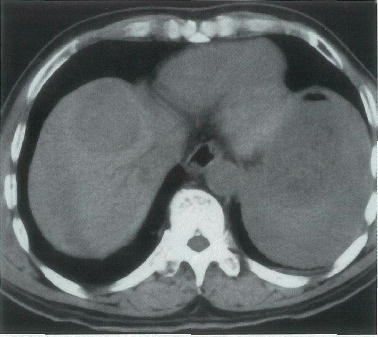

64歳の男性。昨晩から持続する腹痛を主訴に来院した。10年前に肝疾患を指摘された。意識は清明。顔色は不良である。脈拍 112/分,整。血圧 84/60mmHg。血液所見:赤血球 189万,Hb 5.8g/dl,白血球 9600。腹部単純CT(A,B)と造影CT(C,D)とを別に示す。

輸血を開始した後に行うのはどれか。

正解 a

診断 肝癌の腹腔内破裂